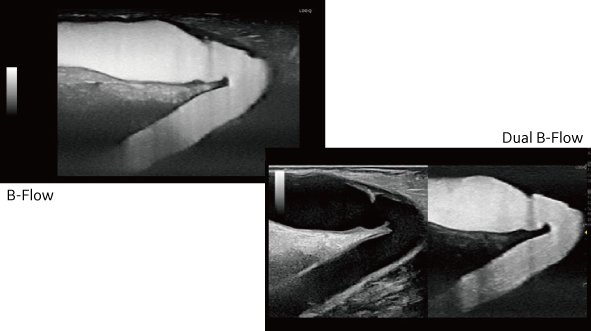

B-Flow

血流信号を増幅するGE独自の技術により微細な血球信号を画像化。

背景のBモードと重ね合わせる「Hybrid」、2画面の「Dual」にも対応し、高精細な血流表示と形態情報の正確な把握を同時に可能とします。